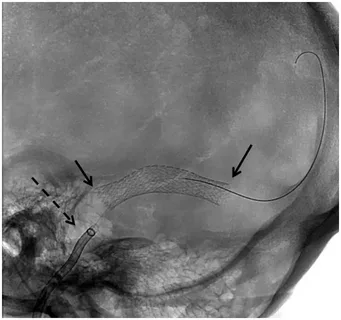

For patients with significant venous sinus stenosis and a documented pressure gradient, placement of a self-expanding stent within the stenotic sinus can restore normal venous drainage, reduce intracranial pressure, and resolve symptoms including pulsatile tinnitus and headache. Dr. Choudhri has published and presented on venous stenting outcomes and is a site principal investigator for the B-SILENT study evaluating the Sonorus Medical stent system

Venous Sinus Stenting